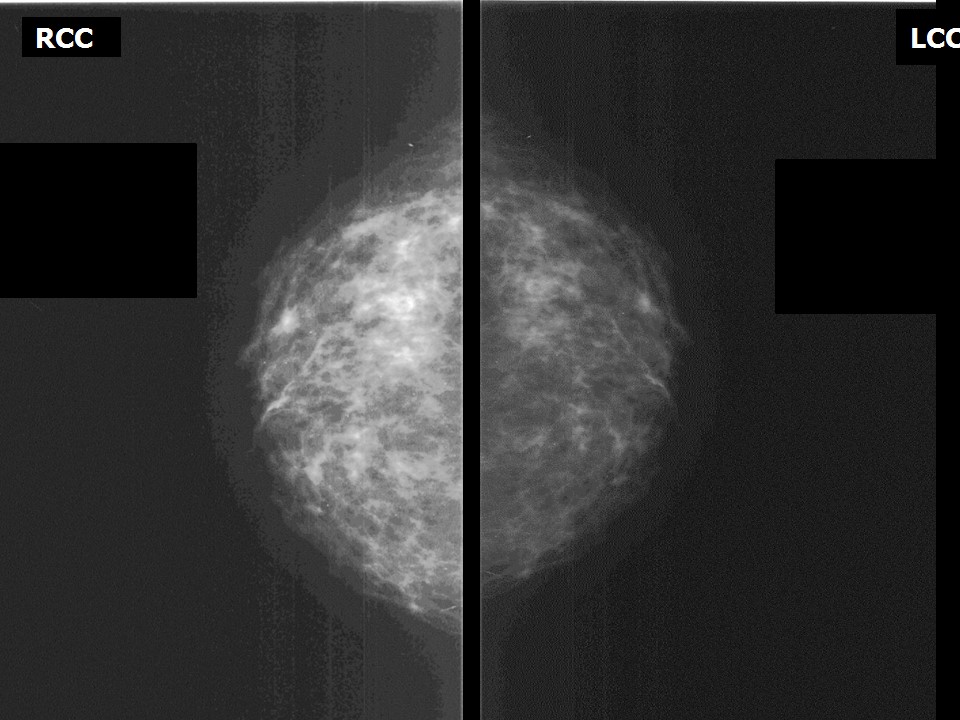

Феномен гипердиагностики в маммографии: примеры и иллюстрации

Раздел: Образы вокруг